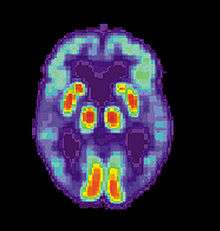

Alzheimer's disease is characterised by loss of neurons and synapses in the cerebral cortex and certain subcortical regions. This loss results in gross atrophy of the affected regions, including degeneration in the temporal lobe and parietal lobe, and parts of the frontal cortex and cingulate gyrus.[52] Degeneration is also present in brainstem nuclei like the locus coeruleus.[84] Studies using MRI and PET have documented reductions in the size of specific brain regions in people with AD as they progressed from mild cognitive impairment to Alzheimer's disease, and in comparison with similar images from healthy older adults.[85][86]

Of the many medical imaging techniques available, single photon emission computed tomography (SPECT) appears to be superior in differentiating Alzheimer's disease from other types of dementia, and this has been shown to give a greater level of accuracy compared with mental testing and medical history analysis.[290] Advances have led to the proposal of new diagnostic criteria.[19][109]

PiB PET remains investigational, but a similar PET scanning radiopharmaceutical called florbetapir, containing the longer-lasting radionuclide fluorine-18, has recently been tested as a diagnostic tool in Alzheimer's disease, and given FDA approval for this use.[291][292]

Amyloid imaging is likely to be used in conjunction with other markers rather than as an alternative.[293] Volumetric MRI can detect changes in the size of brain regions. Measuring those regions that atrophy during the progress of Alzheimer's disease is showing promise as a diagnostic indicator. It may prove less expensive than other imaging methods currently under study.[294]